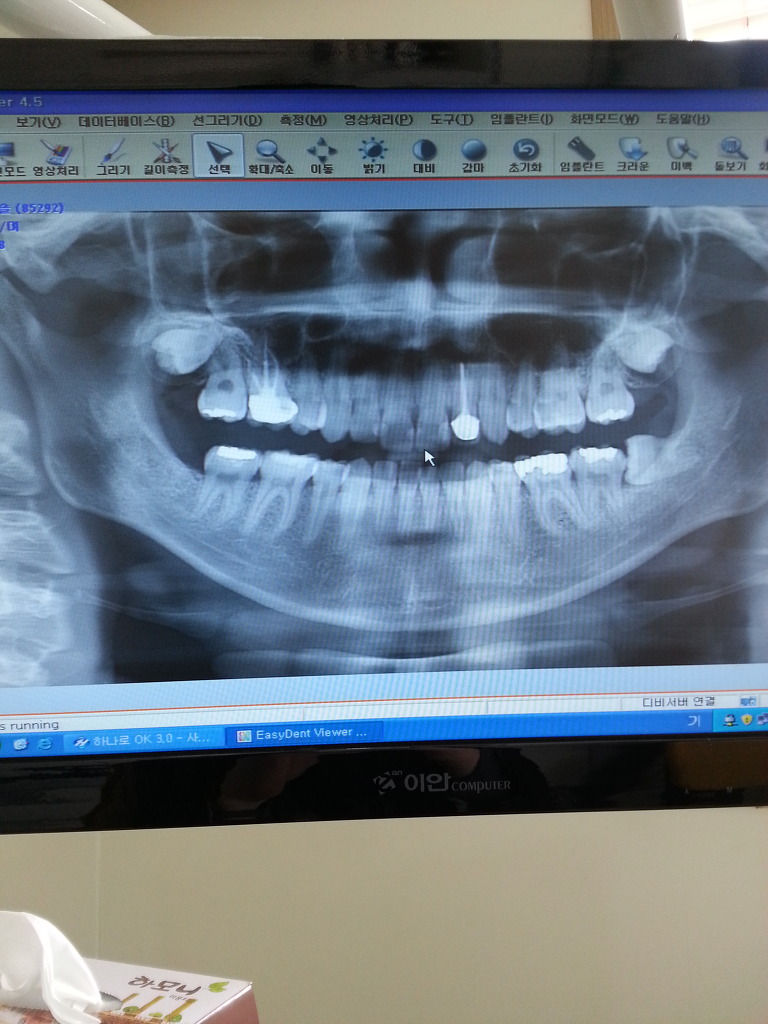

내 사랑니는 이렇게 생겼음

오른쪽에 있는 거 보이지? 실제론 왼쪽 사랑니..

원래 아래쪽에 하나 더 있었는데 그건 뽑아서 사진에 안나옴

신경치료랑 이빨치료한게 적나라하게 나와서 좀 부끄러웠음...

그건 그렇고...사랑니...

시발...존나 크고 아름답네...뽑을라면 아플거같은데 아오..

위에 사랑니 보여?ㅋㅋㅋㅋㅋㅋ2개 더 있잖아ㅋㅋㅋㅋㅋㅋㅋㅋㅋㅋㅋㅋ

나 울뻔했음 시발 ㅋㅋㅋㅋㅋㅋ사랑니 한개 더 뽑으면 6개 뽑는건데

위에까지 뽑아야 되면 8개ㅋㅋㅋㅋ

전체 이빨의 1/4개 아님??ㅋㅋㅋㅋㅋㅋㅋㅋㅋㅋ